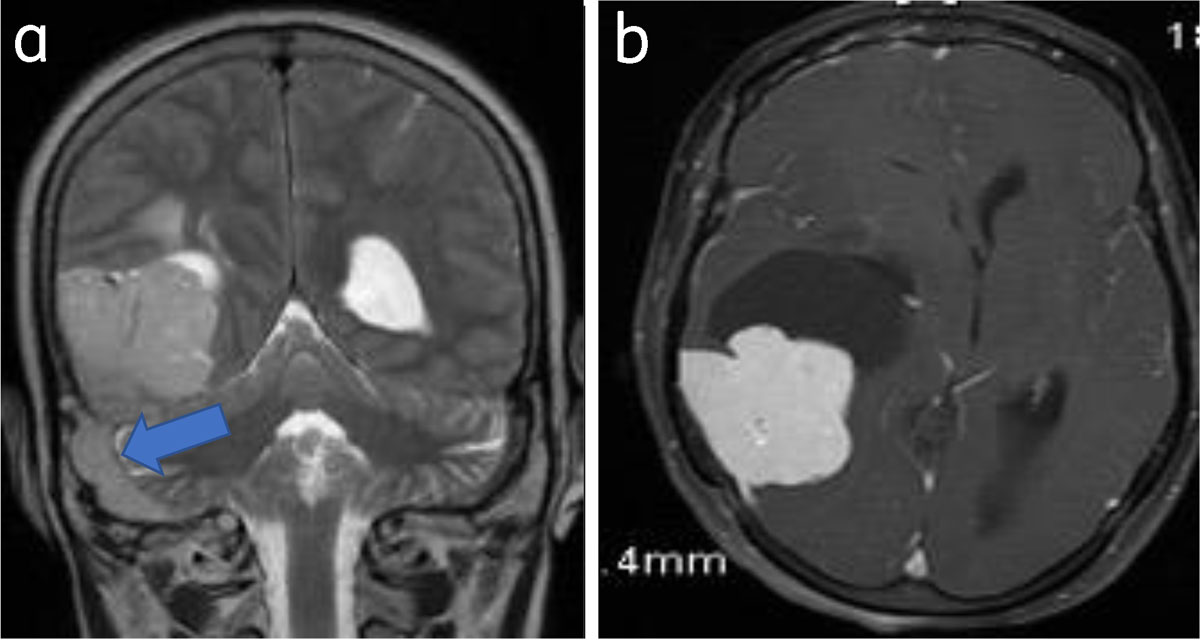

Sinus invasion is the invasion of venous sinuses and is a known complication [2] (Figures 10, 11).

Figure 11

Meningioma with venous sinus invasion: Coronal T2WI (a) and axial (b) post-contrast images show right parieto-occipital meningioma with right sigmoid sinus invasion (arrow).